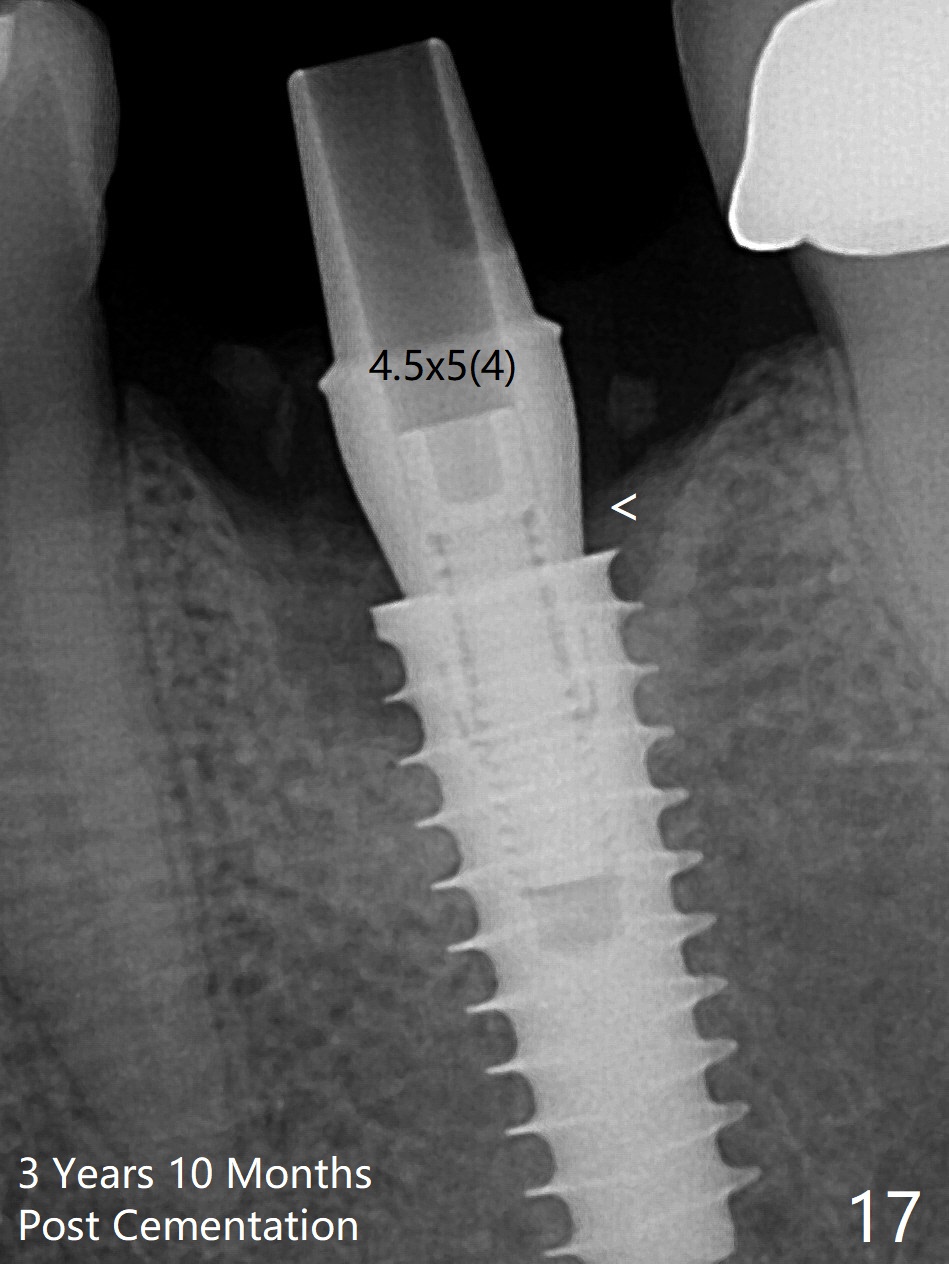

The gingiva looks healthy 8 months postop (3 months post cementation (after abutment screw retightening and addition of porcelain to proximal surfaces, Fig.12).  New bone has apparently covered the implant plateau (Fig.13 arrows). Bone density between threads increases 9 months post cementation (Fig.14).  There is 2 mm bone superior to the implant plateau mesial and distal 1 year 9 months post cementation (Fig.15,16).  The crown/abutment is loose 3 times (3 months (Fig.14), 11 months (between Fig.14 and 15) and 2 years 3 months post cementation).  In spite of being stable 3 years 10 months post cementation, a smaller abutment is placed (Fig.17 (PA), 18 (BW)) with impression for a new crown.  After intraoral cementation, the new crown/abutment is removed for residual cement removal.  When the complex is reseated, it is not smooth, probably due to proximal undercut.  Fortunately the abutment appears to be completely seated, followed by 20 Ncm torque (Fig.19).